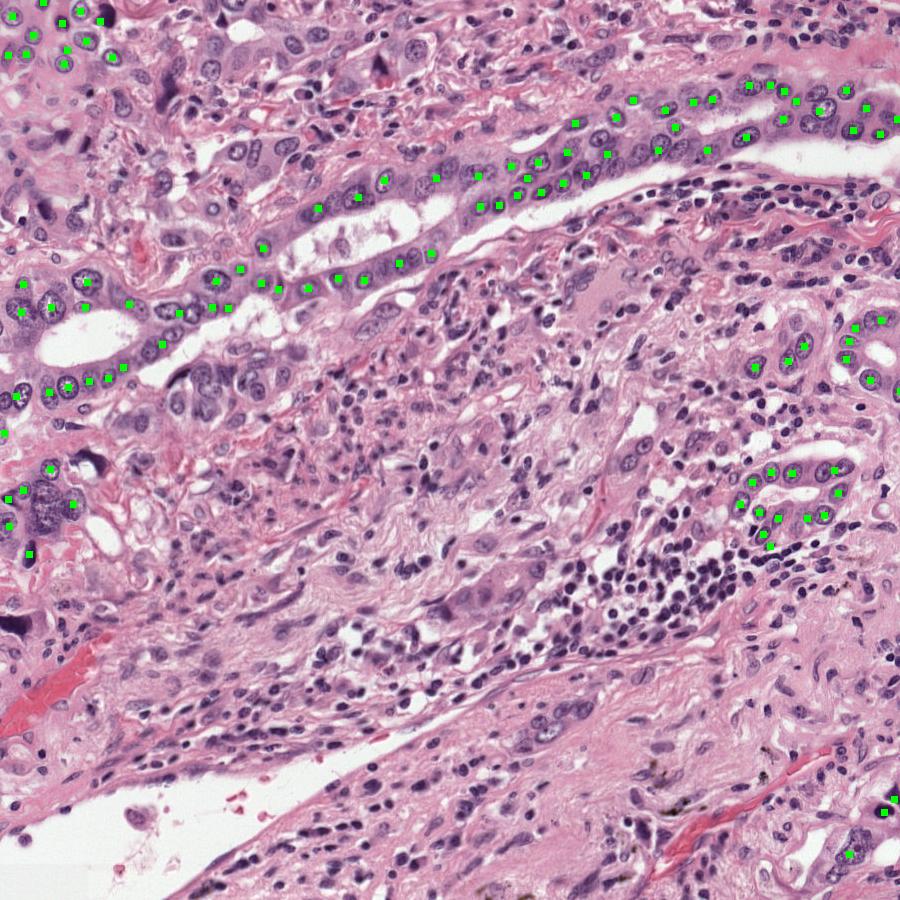

Figure 8: Visual comparison of ground truth and UAM predictions. Tumor cells are highlighted in green.

Refer to caption

(a) Ground Truth1

(b) Prediction1

(c) Ground Truth2

(d) Prediction2

Figure 9: Visual comparison of ground truth and UAM predictions. Tumor cells are highlighted in green.

We provide a visualization of the Ground Truth, BiomedParse-generated, and UAM-generated masks in Figure 7. The multimodal UAM model demonstrates the capability to provide a more accurate mask, which we attribute to its effectiveness in leveraging the cell radiomics information from each image. This finding underscores the significant advantage and effectiveness of the multimodal UAM architecture. More visualization results are shown in Figures 891011, indicating the effectiveness of UAM that highlights tumor cells on H&E slides based on radiomics data, facilitating pathologist interpretation.